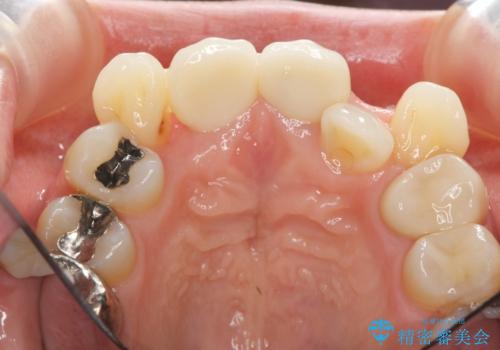

- 26.4万円(ジルコニアクラウン×2・仮歯×2)費用は治療当時の料金となります

清掃を難しくしている歯を抜去することで虫歯の再発を防ぐような治療方針としました。